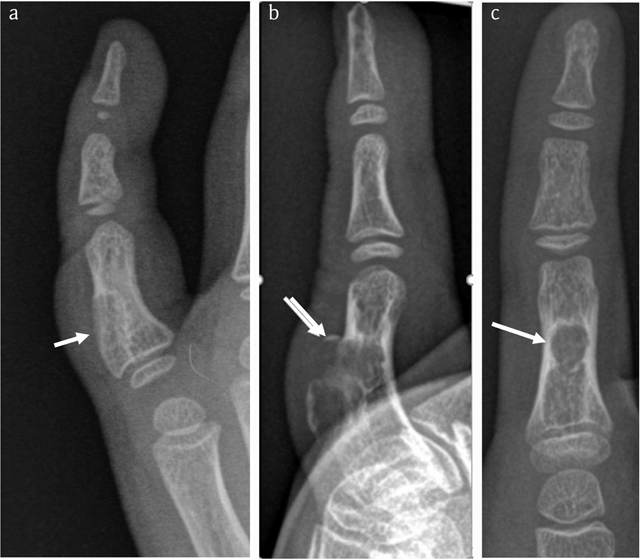

Figure 1

Case 1 – Conventional radiographs of the right fifth finger in a nine-year-old boy. Oblique view taken five years prior to the current admission (a). The lesion (arrow in a) was originally interpreted as a non-ossifying fibroma. Lateral (b) and anteroposterior (AP) view at current admission (c). The lesion has grown and consists of two components. The largest juxta-cortical and exophytic part causes pressure erosion of the dorsal cortex, which is thinned and focally destructed with overhanging edges (arrow in b). There is an associated soft tissue swelling. The smaller intramedullary part consists of a well-delineated radiolucent lesion with sclerotic borders. The latter is best seen on the AP view (arrow in c).